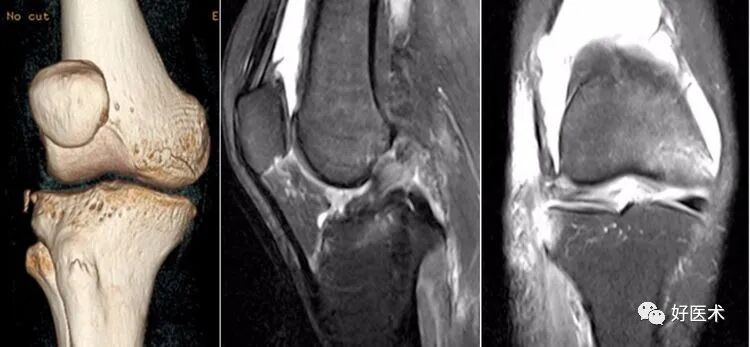

5)Segond骨折:

-

胫骨平台前外侧撕脱骨折(胫骨平台腓骨尖上方,关节线下方的撕脱骨折),多因为下肢过度内翻加内旋暴力所致。

骨折本身无特殊治疗,但其强烈提示ACL损伤(75–100%)。